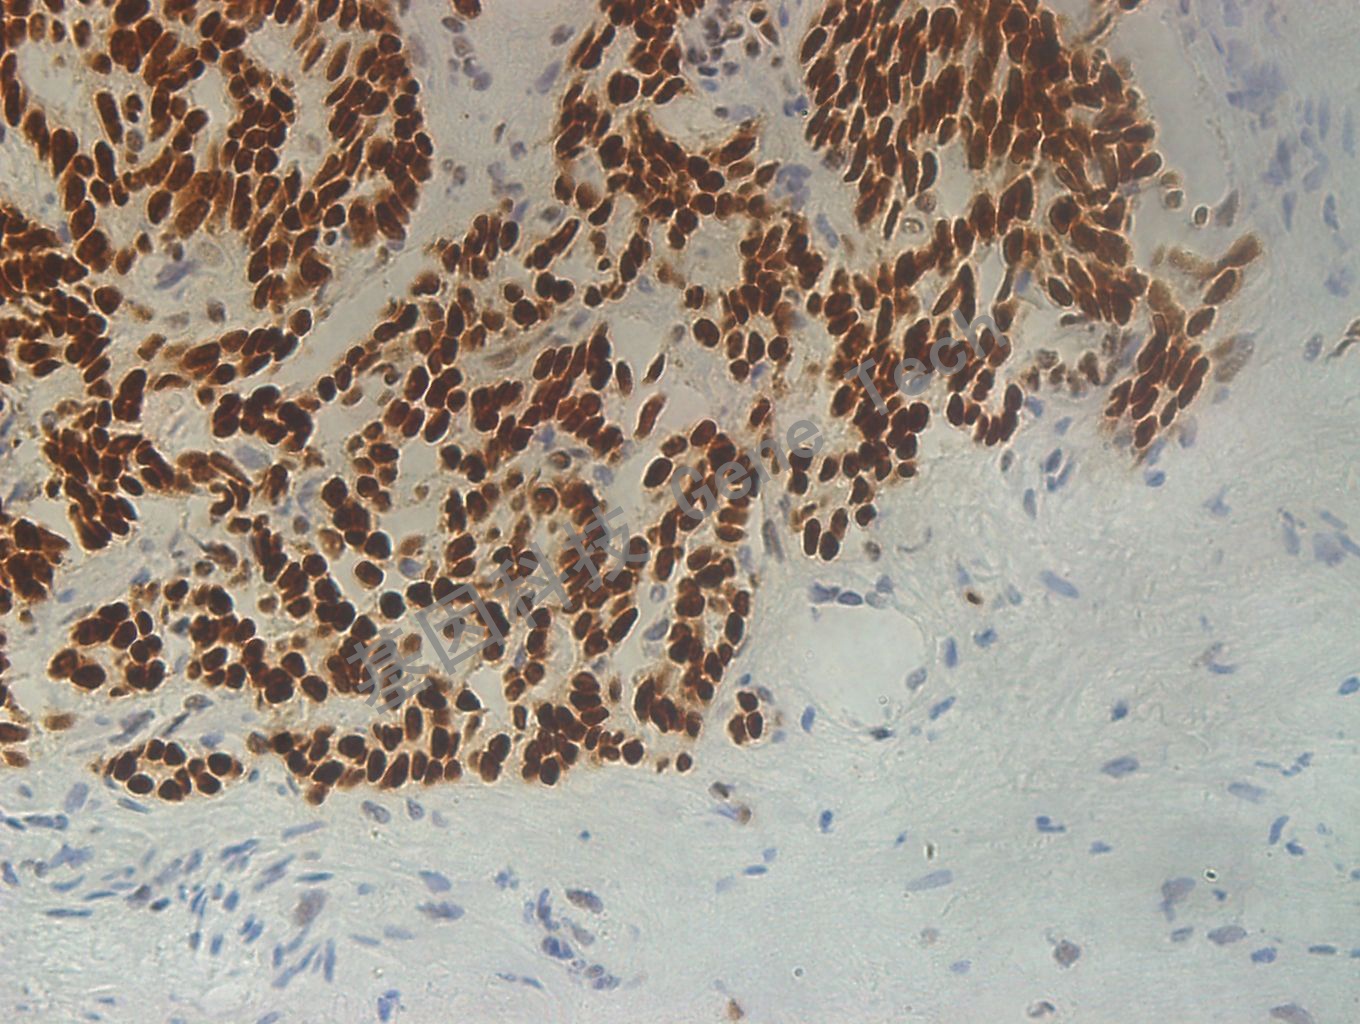

前列腺癌石蜡切片,用 TLE-1(GT2239)染色,细胞核阳性,DAB显色。(40×)